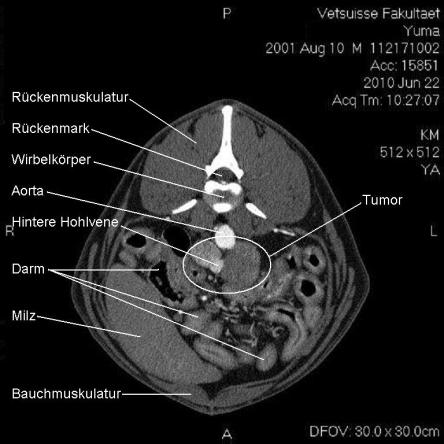

Die Computertomographie (CT) liefert mittels eines röntgenähnlichen Verfahrens ein dreidimensionales Bild des untersuchten Körperteils. Da das untersuchte Tier vollständig ruhig liegen muss, wird Yuma zur Untersuchung narkotisiert.

Im CT wird ersichtlich, dass sich der Tumor, welcher von der linken Nebenniere ausgeht, schon sehr weit in das Gefässystem von Yuma vorgearbeitet hat. Krebsausläufer finden sich wie erwartet in der Hohlvene, aber auch in der Nierenvene sowie in einer weiteren grossen Vene. Der Geschwulst ist somit inoperabel.